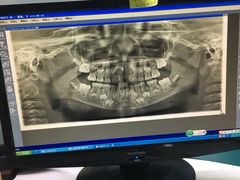

• 天使口腔门诊部(上海店)

• -天使口腔门诊部(上海店)

leo | 19-04-06

yuanera | 19-04-06

cao_only | 19-04-04